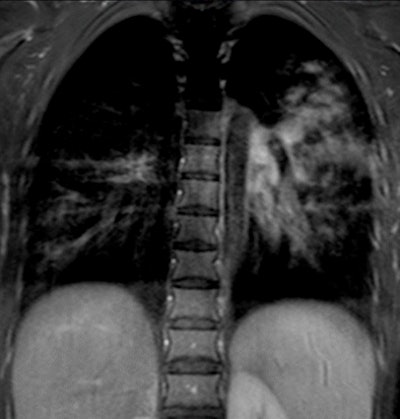

| A 13-year-old girl with pneumonia caused by Mycoplasma pneumoniae. Chest x-ray (above) and a contrast-enhanced 1.5-tesla coronal image (below). The MR image shows patchy parenchymal changes in both lungs. Images courtesy of the Department of Radiology, Turku University Hospital. |